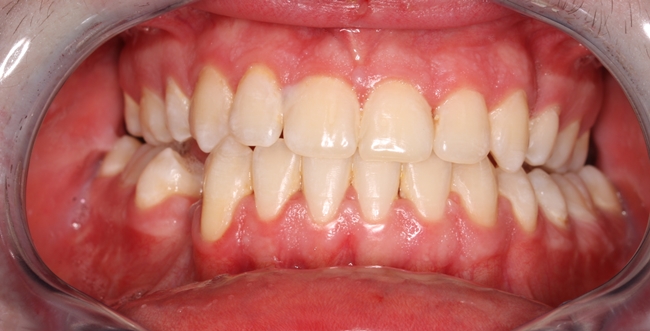

Wady szkieletowe należą do grupy zaburzeń rozwojowych o charakterze zarówno dziedzicznym, jak i nabytym. Ujawniają się najczęściej w okresie dojrzewania, kiedy następuje intensywny skok wzrostowy. Czasami jednak już od najmłodszych lat życia rodzice obserwują, że dziecko ma problemy na przykład z odgryzaniem pokarmu, ponieważ zęby górne i dolne są ustawione w nieprawidłowych relacjach wobec siebie. Jedna z częściej występujących wad gnatycznych, w polskiej nomenklaturze określana jako progenia, manifestuje się tym, że zęby żuchwy są ustawione doprzednio w stosunku do zębów szczęki (ryc. 1, 2). Wada ta może być wyleczona tylko operacyjnie (ryc. 3, 4). Zaburzenia szkieletowe mogą być związane zarówno z nadmiernym rozwojem, jak i niedoborem rozwoju odpowiednich kości. W takich wypadkach najczęściej manifestują się nieprawidłowym zgryzem lub brakiem kontaktu pomiędzy zębami szczęki i żuchwy, co utrudnia funkcjonowanie i skłania pacjentów do poszukiwania pomocy.

Ryc. 4. Zgryz po zakończeniu leczenia.